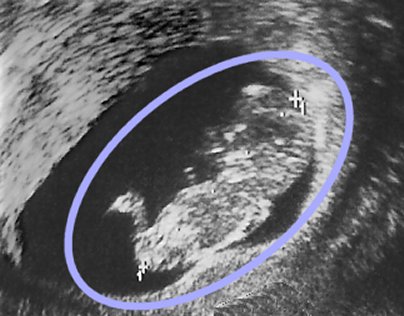

Tento sonogram pořízený ve třetím měsíci těhotenství ukazuje mužský plod (hlavu, tělo a nohy je možné jasně rozeznat uvnitř modrého oválu).